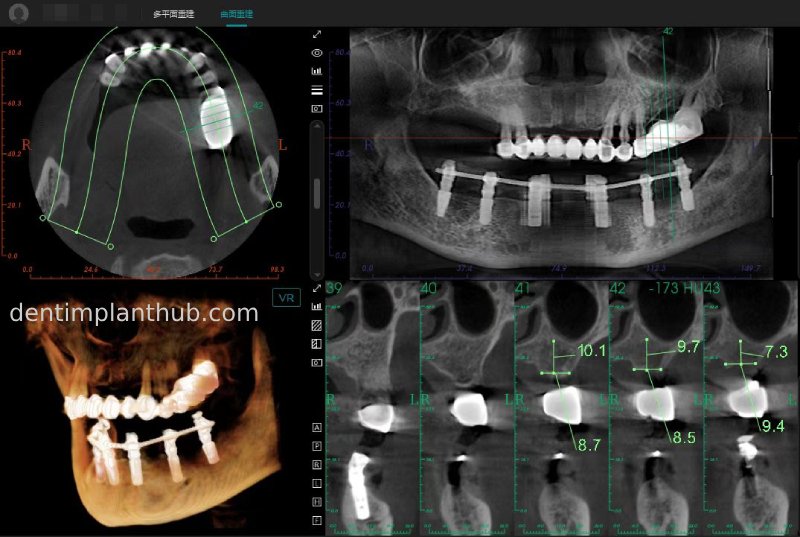

CBCT review results on 13 May '24

46

44

42

32

34

36